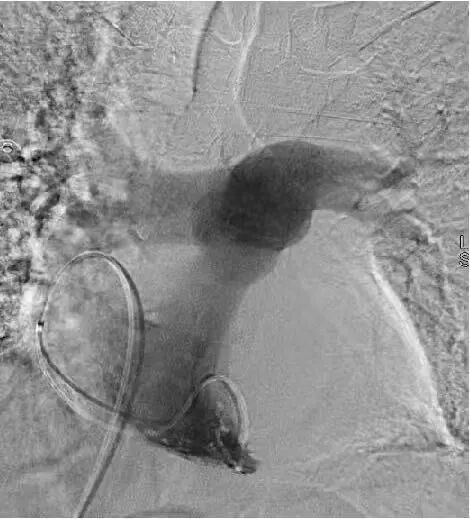

介入醫(yī)學(xué)團(tuán)隊緊急制定手術(shù)方案,一場與死神賽跑的介入治療隨即展開。手術(shù)分三步精準(zhǔn)推進(jìn):

最后通過肺動脈造影,精準(zhǔn)實施取栓、碎栓操作。

整個手術(shù)僅用一個半小時便順利完成,血栓被徹底清除。術(shù)后效果立竿見影,小李的胸悶、憋氣癥狀明顯緩解,咳嗽咳痰好轉(zhuǎn),右下肢疼痛也有所減輕。